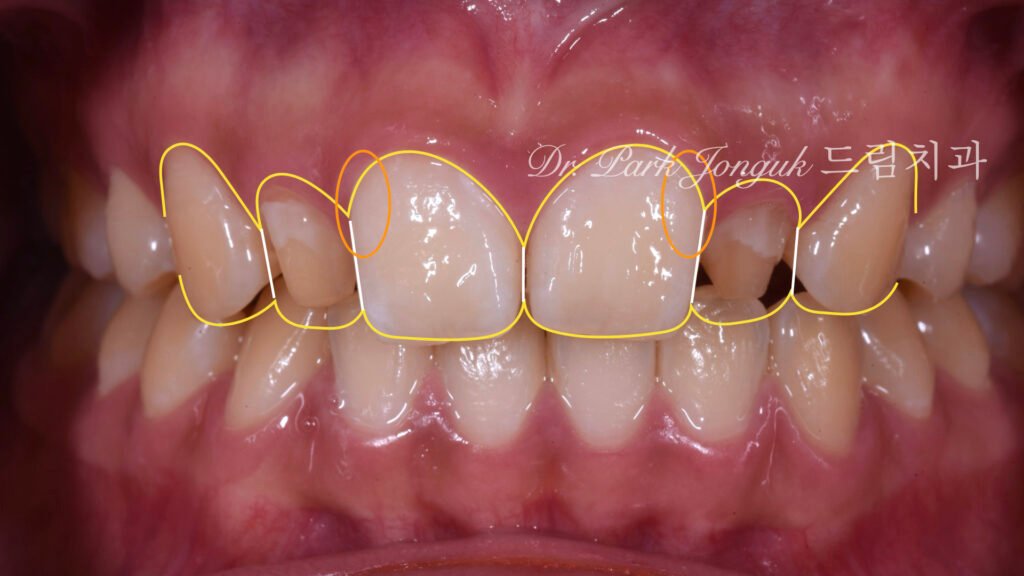

옐로우 스테인의 적용 중절치의 치경부(잇몸 근처 영역)에 옐로우 스테인(yellow stain)을 전략적으로 적용했습니다. 이는 여러 효과를 만듭니다:

- 자연스러운 뿌리 형태 재현: 실제 치아처럼 치경부로 갈수록 색이 진해지는 그라데이션을 만들어 생물학적 사실성을 높입니다.

- 비후 치근의 시각적 보정: 굵은 치근으로 인한 두툼한 인상을, 색상 변화를 통한 시각적 깊이감으로 상쇄합니다. 약간 진한 톤은 그림자 효과를 만들어 윤곽을 더 자연스럽게 보이게 합니다.

- 입체감 부여: 단색 세라믹은 평면적으로 보이지만, 내부 특성화(internal characterization)를 통해 치아에 3차원적 깊이가 생깁니다.

비후 치근 문제의 해결: 중절치 치경부에 적용된 옐로우 스테인이 예상대로 작동했습니다. 굵은 치근으로 인한 두툼한 인상이 색상 그라데이션을 통해 자연스러운 뿌리 형태로 인식됩니다. 실제로 치근의 물리적 두께는 변하지 않았지만, 시각적으로는 자연 치아와 구별이 어려울 정도로 개선되었습니다.

심미적 통합: 전체적으로 인위적인 느낌 없이 자연스러운 치열로 보입니다. 치경부의 색상 변화, 표면의 미세한 질감, 적절한 투명도 등이 조화를 이루어 “라미네이트 했다”는 인식을 주지 않습니다.